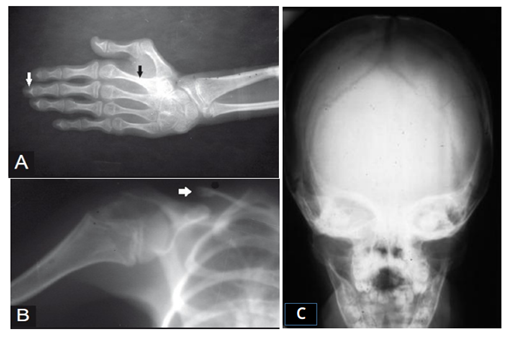

Most children with Progeria are usually born healthy, but they begin to show many signs and symptoms of the disease within the first 2 year of life. Child with Progeria failure of growth and development or gain weight normally They develop many physical feature including: aged-looking skin, a bigger head, large eyes, a small lower jaw, a thin nose with a "beaked" tip, ears that stick out, visible veins, slow and abnormal tooth growth, a high-pitched voice, loss of body fat and muscle, skin atrophy, hair loss including eyelashes and eyebrows, stiffness of joints as shown in Figure 3. Children have a remarkable similar appearance despite differing ethnic backgrounds.3

The pediatrician may recognize Progeria based on signs and symptoms characteristic of the syndrome during a routine checkup as symptoms of Progeria are very noticeable. Initial clinical evaluation such as child’s appearance and medical records can help to point the condition. The Progeria Research Foundation has a Diagnostic Testing Program: to identify the specific genetic change, or mutation, in the Progeria gene that leads to HGPS.2 Physician will perform an audio-gram, vision acuity test to check hearing and vision. The Baby’s Growth and Development chart to track the developmental milestones of the children and concerned in specialist of medical genetics (if needed).6 X-ray to identify the deformities and bone changes showing in Figure 4. Blood test to check for a mutation on the specific gene responsible for Progeria.13,14

Blood investigations were normal except for increased serum cholesterol and increased urinary excretion of hyaluronic acid. The child was subjected to a skeletal survey to confirm the diagnosis. Radiographs of the skull showed diastasis of the sagittal suture with numerous wormian bones. The mandible showed the hypoplastic with infantile angle and the chest showed sloping ribbon-like ribs with thinning of both third ribs posterior. The lateral half of both the clavicles was absent. The dorsal spine in the lateral projection showed presence of fish mouth vertebrae. The hands and feet revealed resorption of terminal phalanges. The above radiological findings confirmed the clinical diagnosis of Progeria.20